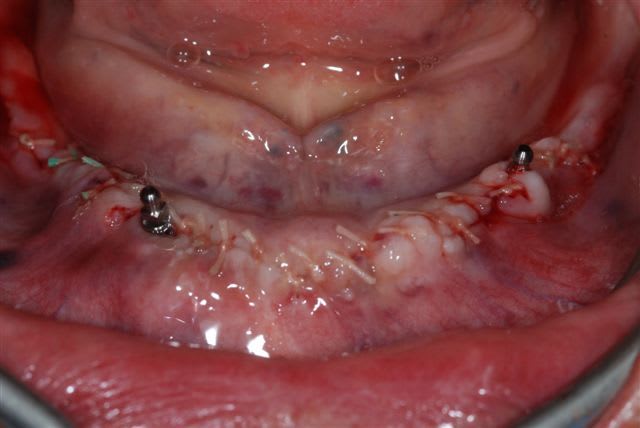

un petit cas clinique de cet après midi:

28/06/2008 à 19h08

suite

la pano post op

j'avais prévu de faire une MCI mais le manque de stabilité primaire des 2 implants côté droit m'en a dissuadé.

membrane biomend extend stabilisée par 2 petites vis de 4 mm de long de chez esasy implant. Os autogène et un peu de bio-os mélangé pour combler le defect.